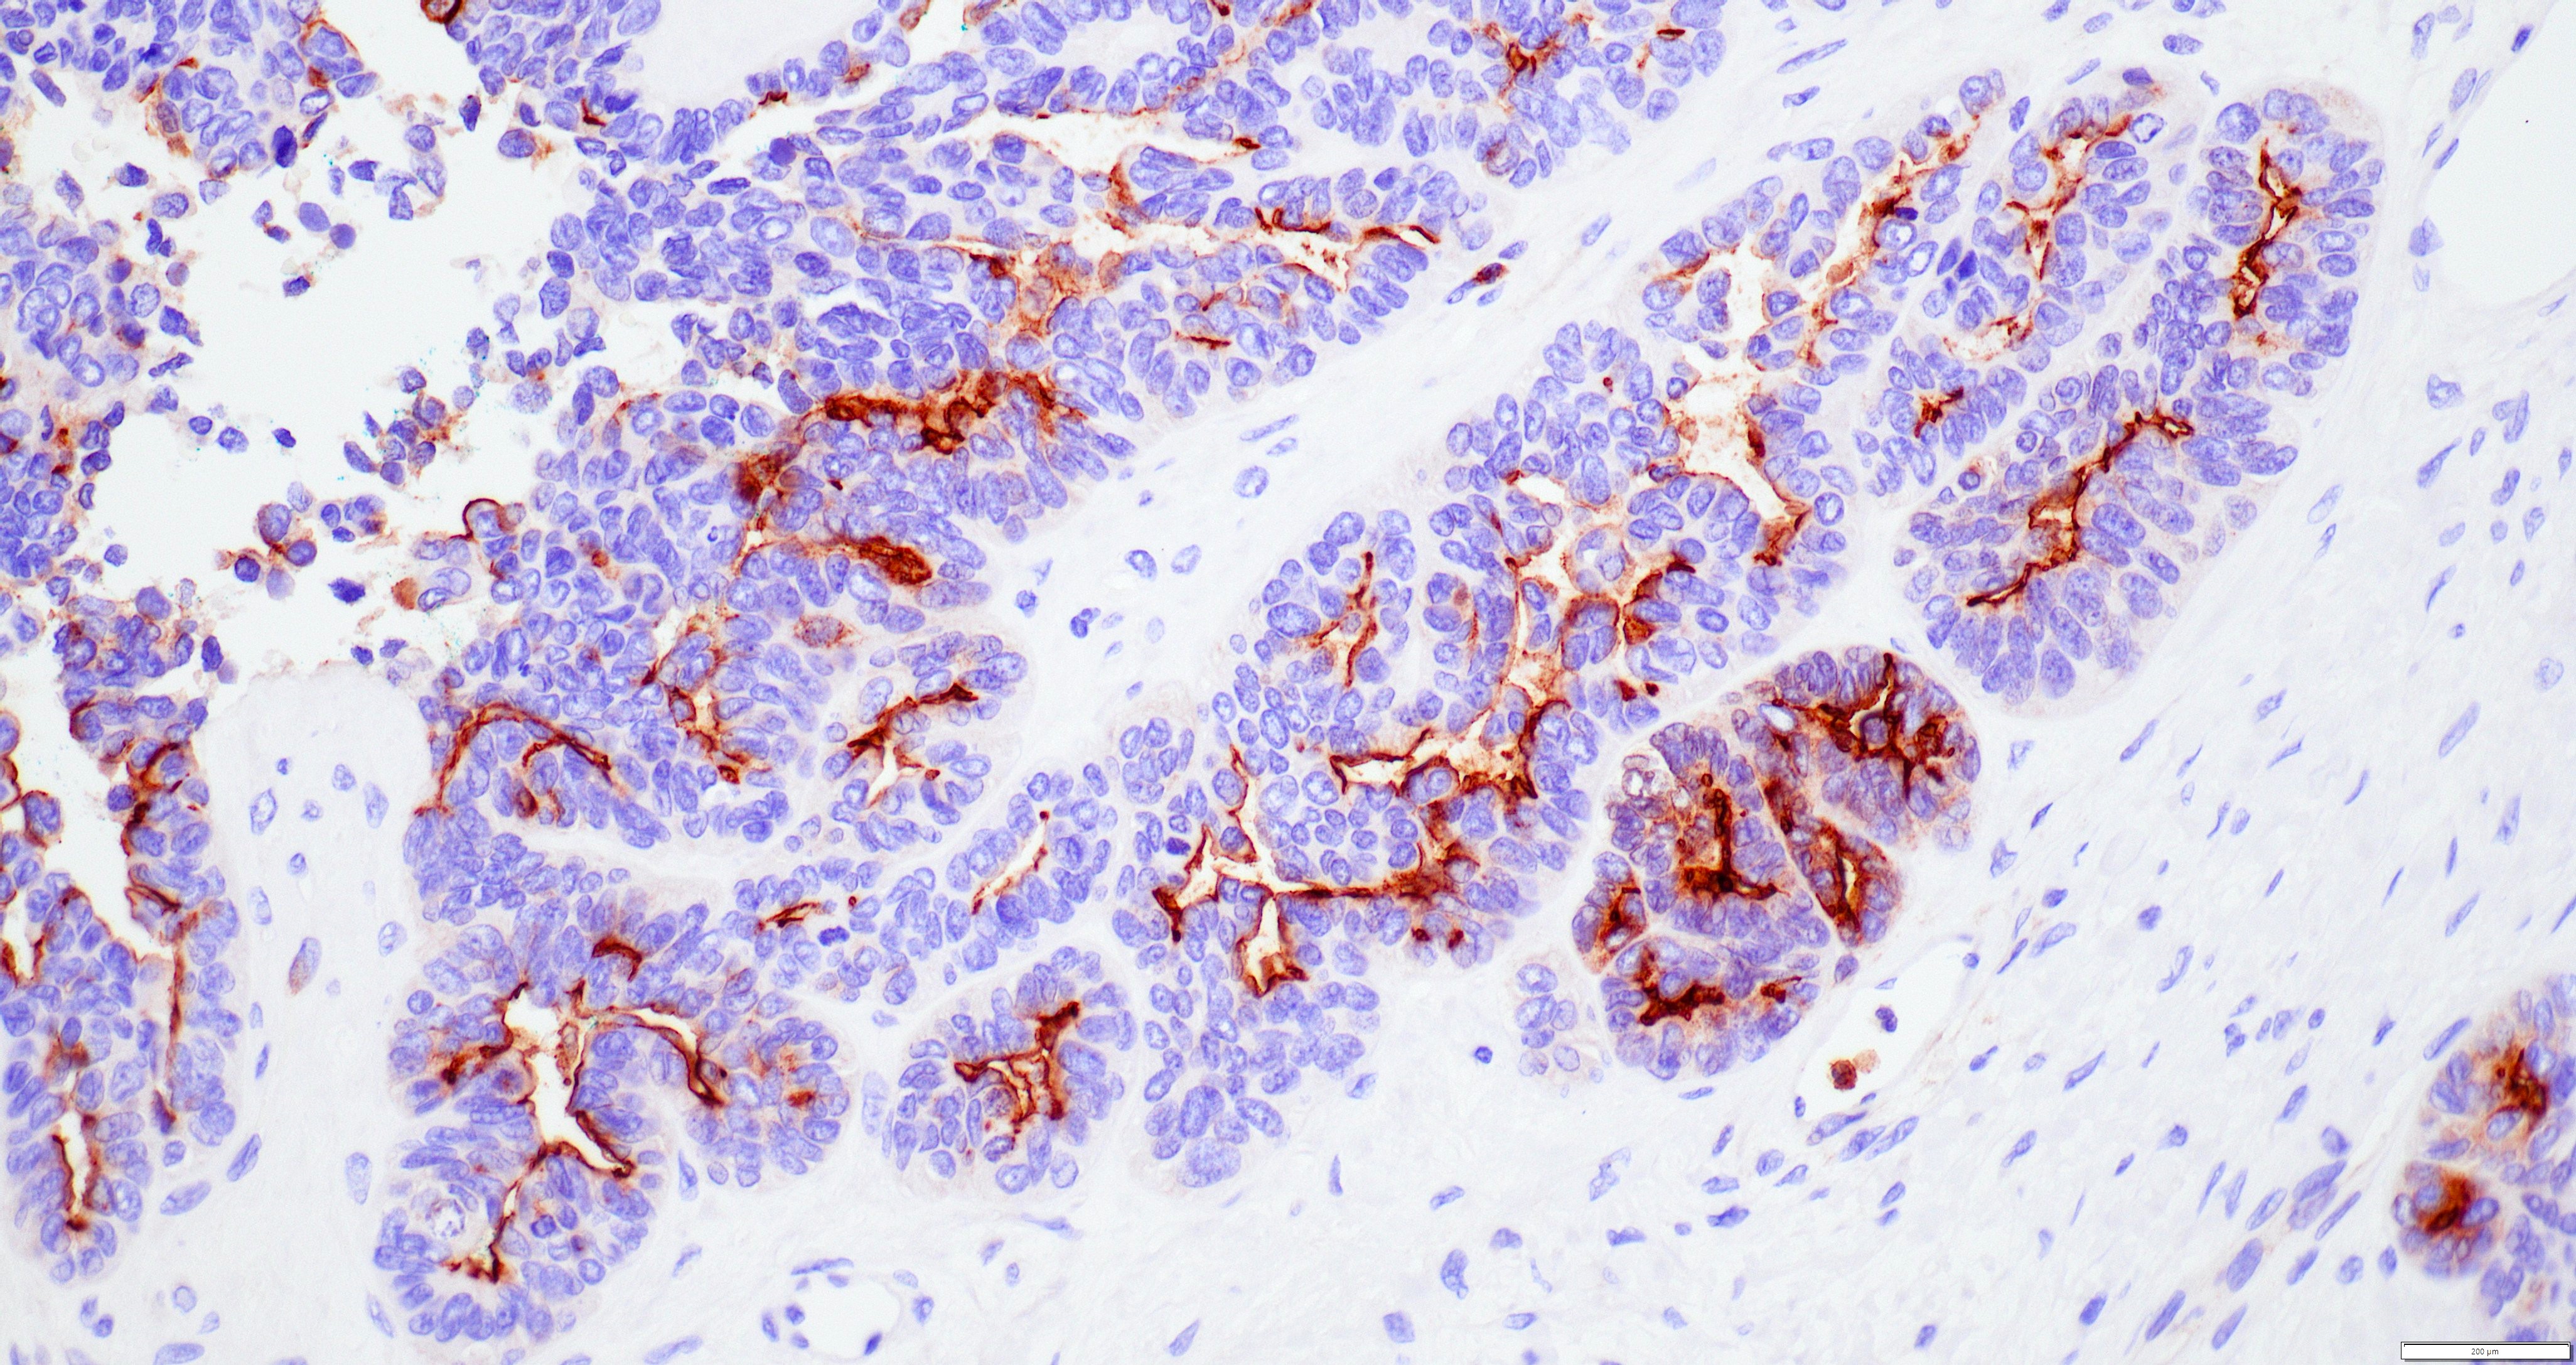

Microscopic (histologic) images

Contributed by Daniel Graham, M.D., Adele Wong, M.B., B.Ch., B.A.O. and Lucy Ma, M.D.

Positive stains

- PAX8: usually diffusely positive

- GATA3 and TTF1: focal or diffuse with inverse staining pattern described in several studies in the most recent WHO classification; cells positive for GATA3 are negative for TTF1 and vice versa (Am J Surg Pathol 2018;42:1596)

- CD10: focal and apical / luminal